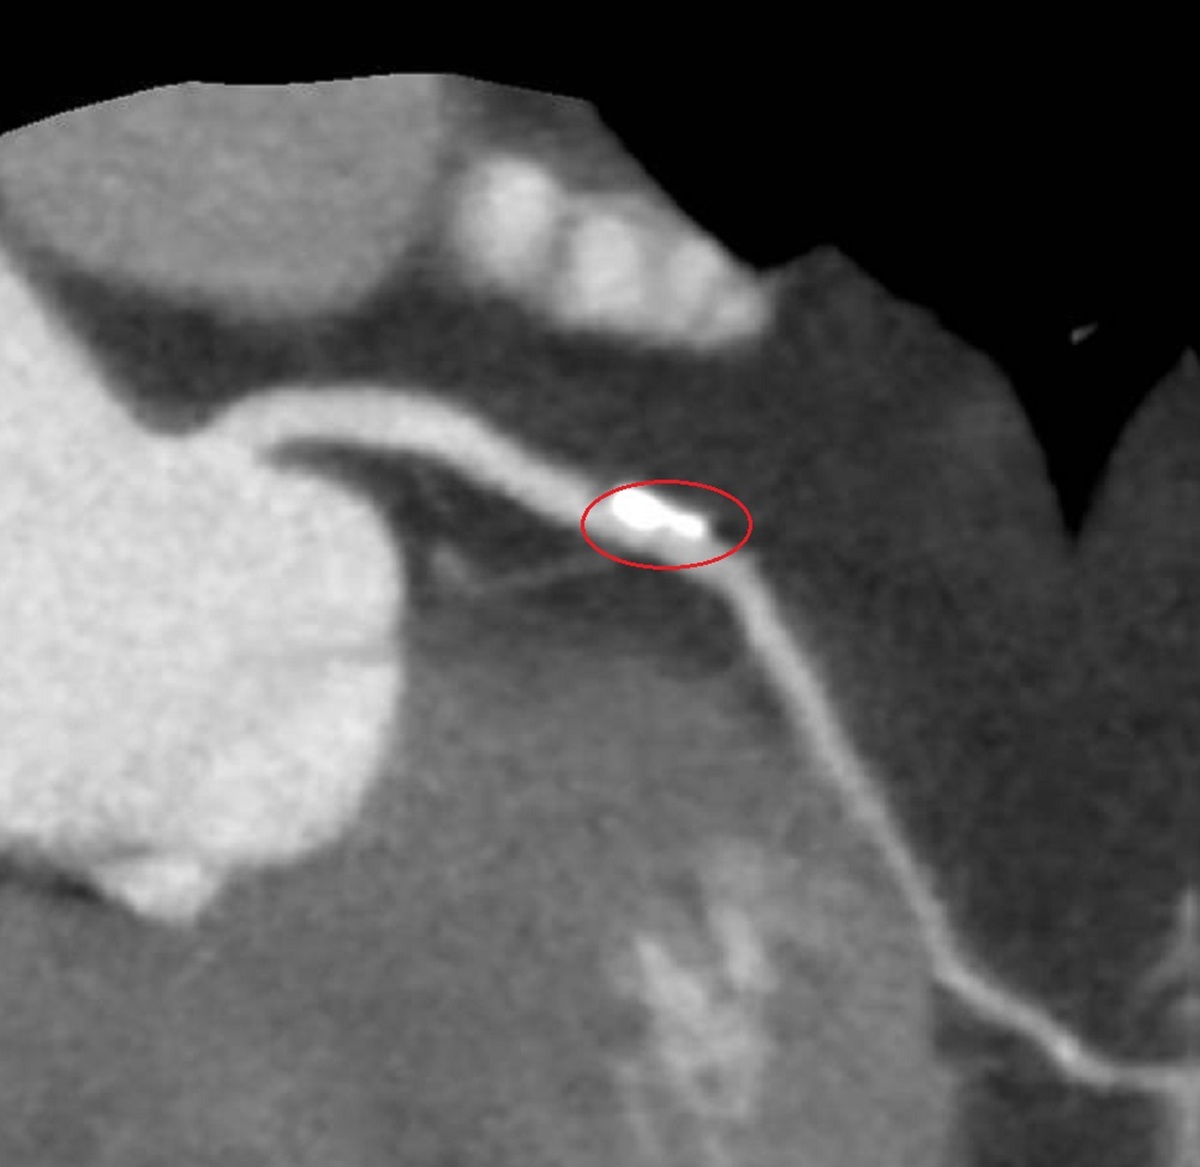

李學林說,運動心電圖發現盧女士心血管缺血,電腦斷層發現左冠狀動脈的左前降支有一處約70%阻塞並鈣化,與病人共同決策,採IVL處理鈣化斑塊,再植入生物適應性支架,預期可達到最佳治療效果。